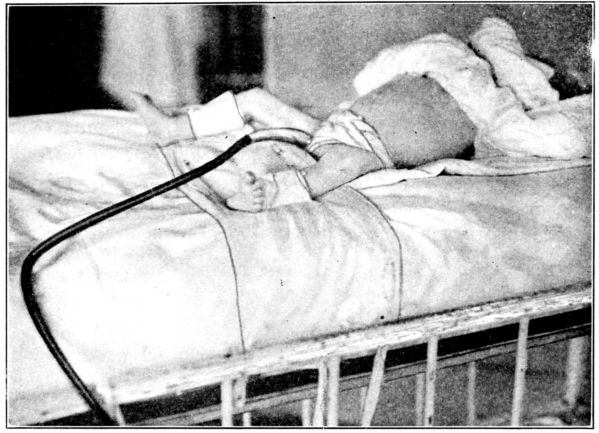

| 177. | Putting the baby in a wet pack | 521 |

| 178. | Baby in wet pack | 522 |